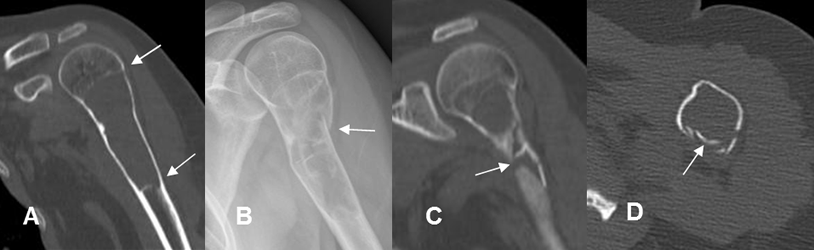

Fig 139 A. Quiste óseo simple.

A: Rx AP y B: Rx axial. Paciente de la Fig 136, con sutil imagen radiolúcida en el fémur proximal.

C: Rx AP. Meses después, presenta fractura patológica subtrocantérica.

Fig 139 B. Fractura patológica.

A: TAC reconstrucción coronal. Alteración en la medular del tercio proximal del húmero, por quiste óseo simple.

B: Rx AP, C: TAC reconstrucción coronal y D: TAC axial. Después de un trauma directo se identifica deformidad y solución de continuidad en la parte posterior, por fractura patológica y conminuta.